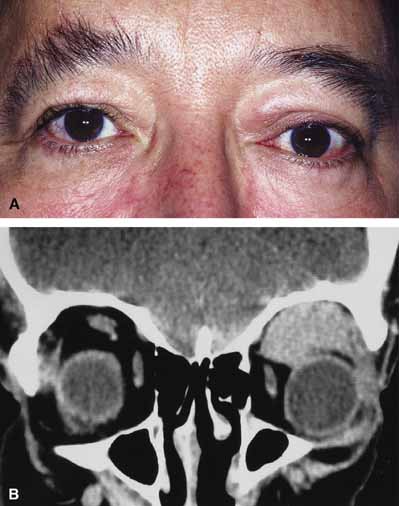

Venous flow malformations (so-called varices) generally refer to those vascular malformations with weakened segments of the orbital venous system, of variable length and complexity.76,77 They may appear as superficial, deep, or combined lesions and may be of a distensible or nondistensible variety. Because they are intrinsic to the systemic circulation, distensible primary varices enlarge with increased venous pressure, and their distensibility varies with the residual thickness and strength of their wall. The lesions often cause intermittent proptosis, pain, and/or bruising because of expansion brought about by physical effort (straining, Valsalva maneuver) or bending (Fig. 10A, 10B and 10C).78 Sudden proptosis may result from hemorrhage into one of the varices or the creation of a one-way valve effect trapping blood within the lesion. High-dose steroids, canthotomy, and cantholysis may be of benefit to decrease the orbital pressure. Direct surgical excision is difficult because of the tortuous tangles of fragile, thin-walled malformed vessels and their tendency to rupture and bleed excessively.59 Nondistensible varices may also appear as superficial, deep, or combined lesions. Clinically they are similar to lymphangiomas and characterized by episodes of acute exacerbation and remission related to hemorrhage or thrombosis within the lesion. Hemorrhage into deeper lesions causes sudden proptosis, pain, decreased motility, and reduced vision. Profound orbital hemorrhage with visual deterioration and pain is treated in a manner similar to that of lymphangioma and orbital hemorrhage (canthotomy, cantholysis, and/or orbital exploration with evacuation of clotted blood and excision of the associated lesion).

Fig. 10 A. A 68-year-old female presented with intermittant proptosis occurring on bending over. B. Multiple, oval shaped, contrast-enhancing masses are present in the right orbit. The masses enlarged with valsalva and were consistant with a diagnosis of orbital varix. C. Multiple, oval shaped, contrast-enhancing masses are present in the right orbit. The masses enlarged with valsalva and were consistant with a diagnosis of orbital varix.